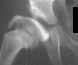

At 5 + 8 years of age

,

a clinical diagnosis of Charcot-Marie-Tooth disease was made, and Shelf

arthroplasty was performed to increase the femoral head coverage.

On the last evaluation (10 years old), the patient was pain free, and showed

acceptable range of motion, however, his right limb is 3 cms. short and

the patient is wearing a 2 cm. shoe lift.